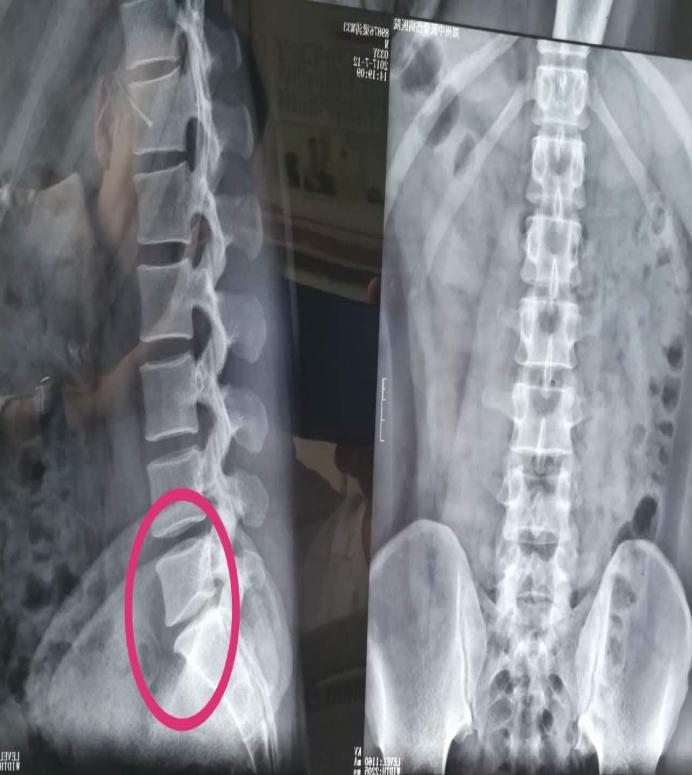

西安市某中学王老师觉得腰部僵痛,刚开始她以为是批改作业劳累所致,便自行购买膏药贴敷。这几天随着气温走低,王老师的腰痛已由腰部放射至腿部,一节课四十五分钟的站立就让她疼痛难忍,于是便来到西安市中医医院针灸推拿康复科安军明主任医师门诊就诊,经过腰部CT检查,王老师确诊患了腰椎间盘突出症。